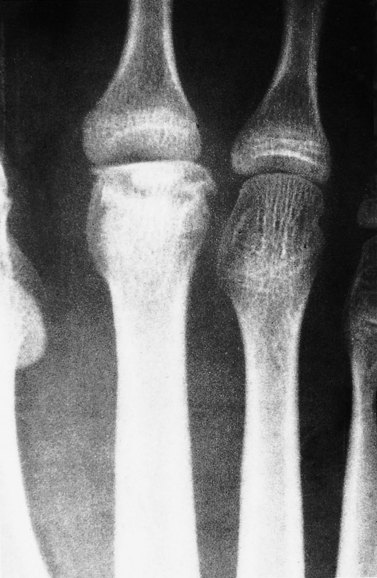

Freiberg’s disease

Freiberg’s disease (lesion) is an osteochondrosis of the 2nd metatarsal head, most commonly seen in young ballet dancers. Pain occurs over the bony head of the metatarsal (contrast this with Morton’s neuroma which gives pain between the metatarsals) and is aggravated by raise onto the ball of the foot. In longer standing cases x-ray reveals flattening of the metatarsal head with damage to the epiphyseal plate. Initially no changes may be apparent on radiographs (Fig. 12.11), with bone scan or MRI being more sensitive. Management is by modification of weight bearing activities and padding over the metatarsal head to offload the joint and reduce direct pressure over the painful area. Orthotic prescription is often required.

image

Figure 12.11 Freiberg’s disease of the metatarsal head.

From Dandy and Edwards (2009).